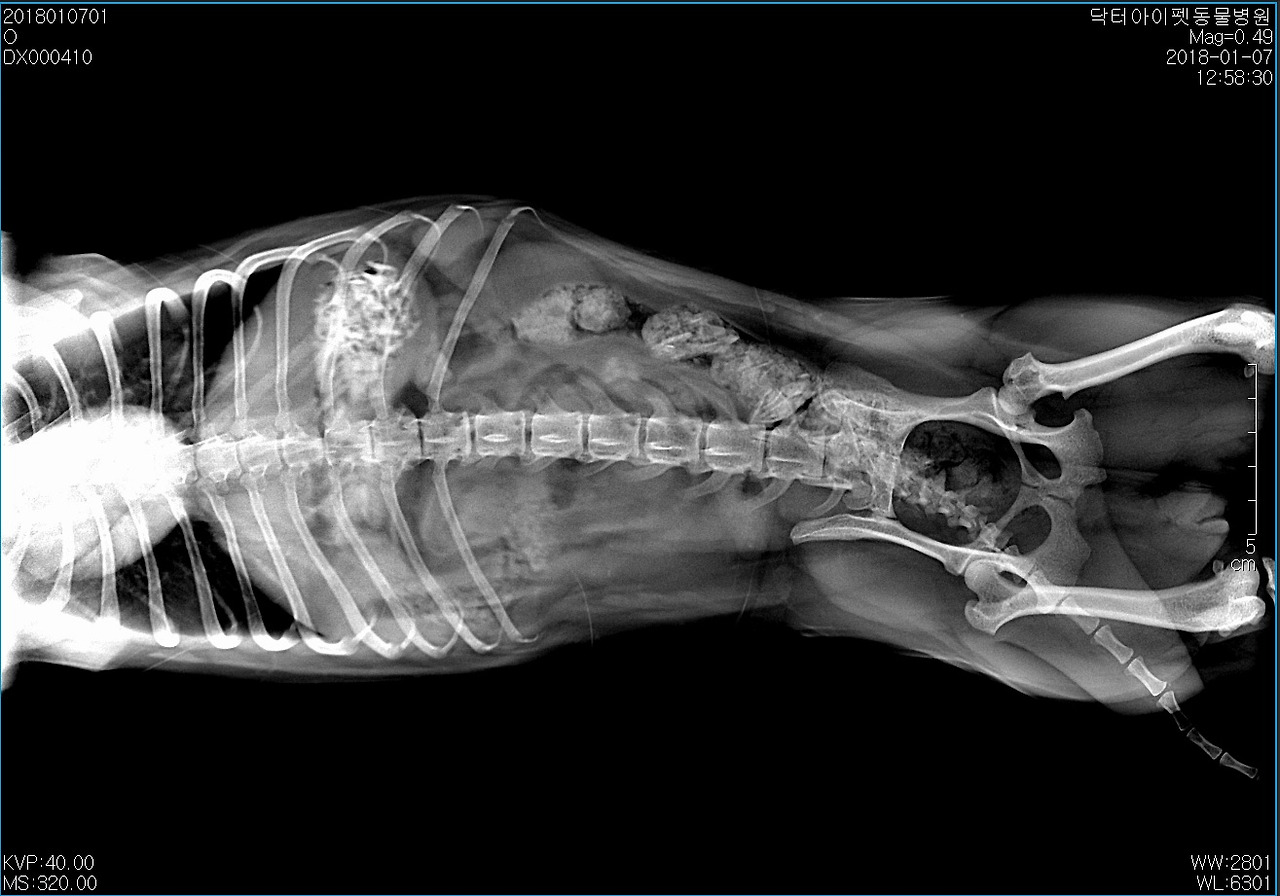

엑스레이를 찍어봤다. 위 한 가득 치킨 뼈가 차있었다. 일반적인 케이스라면 수술을 우선적으로 고려했을 거다. 다행스럽게도 띠띠는 침을 많이 흘리거나 출혈성 구토, 혈변 등의 증상이 없었다. 절대 금식을 당부하고 3일 통원치료를 계획했다. 72시간 정도 경과하면 대부분 섭취한 음식물은 소화되기 따름이다. 기대한 대로 대부분 소화되어 대변으로 배출되었다.

통원 1일, 2일, 3일차 방사선 사진. 다행이었다. 뼈는 모두 소화되고 배출되었다.